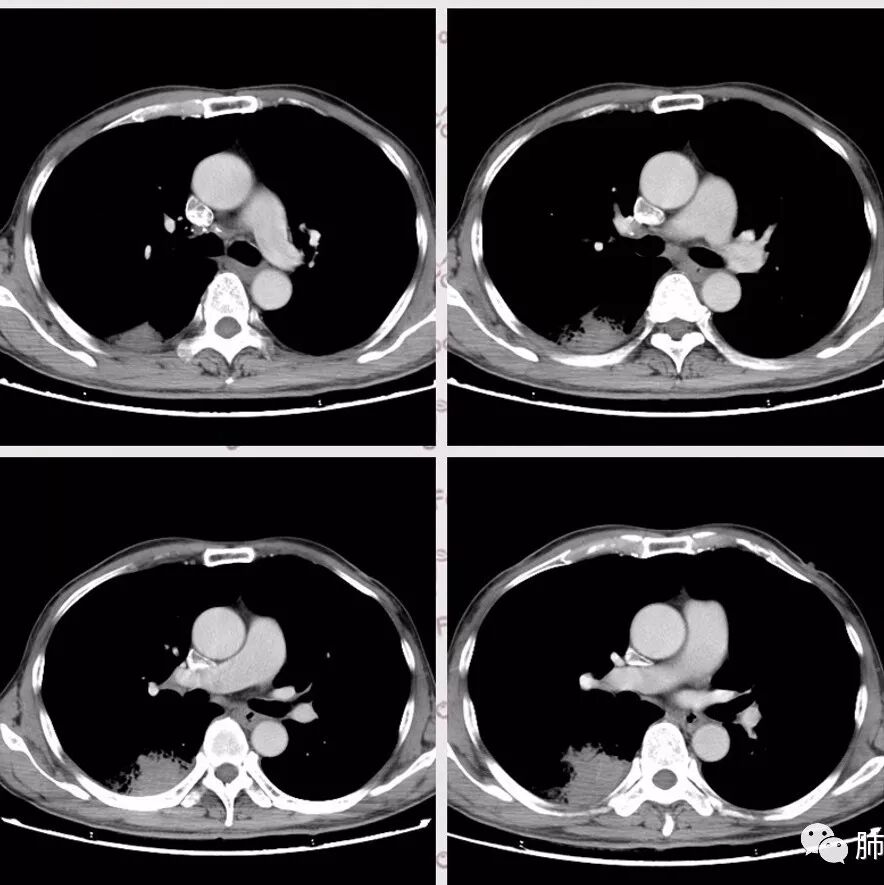

右肺下叶团块状密度增高影,边缘模糊,其内见液性低密度影,多发小气泡影及充气支气管征,考虑肺脓肿。颅内双侧顶叶长T2长T2病灶,周围水肿,DWI高信号,增强扫描囊壁环形强化,囊壁钙化,周围水肿,考虑脑脓肿。患者长期接触垃圾,什么菌都有,肺、脑脓肿,考虑肺克。再有肝脓肿就更支持了。

慢性病程,体质一般、接触垃圾,右下肺长轴与胸膜平行肿块,近肺门侧液化坏死伴多个小圆型空泡,肿块密度不均、不均匀强化,周围少量胸膜增厚,脑内多发空洞灶,考虑肺脑脓肿。鉴别肺腺癌脑转移。

头是脓肿,没有糖尿病;胸膜下分布为主,轻中度强化,实变中坏死,结合头颅表现,考虑隐球菌病,肺克。

胸部CT:右肺下叶背段实变,广基底,糊墙,长轴与胸膜平行,周围晕,支气管进入堵塞,纵隔窗可见低密度坏死,实变内小空洞?脑部不会看。

胸CT:右肺下叶背段实变影,内可见小空泡,病灶与胸膜呈宽基底,实变病灶周围存在毛玻璃影,纵隔窗可见病灶内存在低密度,增强可见病灶强化,并见病灶内低密度区。头MRI不会看。

右肺下叶背段实变,广基底,糊墙,长轴与平行胸膜,周围有晕,支气管进入堵塞,可见低密度坏死及小空泡。颅内多发环形强化灶,符合脑脓肿三层结构,结合临床,考虑:感染性病变,隐球菌?鉴别肺克。

肺内类三角形稍高密度病灶,边缘模糊,其内看见两个小气泡影。增强扫描欠规则厚壁中度强化,其内有轻度强化或未强化区。符合肺脓肿表现。

右肺下叶见不规则软组织影,边缘不清,内夹杂气体,背段支气管未见明显阻断,增强扫描下叶病灶内见类圆形低强化区,其边缘光滑,见低强化区壁,颅脑左侧枕叶及双侧顶叶见多发长T1长T2信号,T2高信号内见类圆形异常信号,壁呈低信号,DWI环形壁未弥散受限,内容物弥散受限,周围为水肿区,增强扫描呈多发环形强化,考虑血源型感染,颅内及右肺下叶脓肿形成

蔡磊:

肺部病灶有收缩性,支持感染性病变,但是患者病程不急,不支持肺克

右肺下叶大片实变

我们回头看肺内的,病灶位于下叶背段,可惜没重建

近肺门区见一坏死腔,内壁较清楚,空泡在周围

单从这个坏死我们分析:1、炎性?2、鳞癌?

局部部分边缘膨隆,欠光滑

不是单纯的近端堵塞,远端不张,远端实变,宽基底

远端实变区膨隆,部分似有栽赃的趋势

南边:

一般来说炎性空洞坏死,空洞偏内的结核多,癌性空洞一般是远端的缺血坏死,这个病例特殊,近端支气管显示不清,内壁部分清晰,部分不清晰,是不是层厚的问题?

炎性有。从总体来说,病变分两部分,靠肺门这里是一个弧形的。从影像来说,确实有些壁不是很清楚,层厚、窗宽窗位影响,这个壁细节显示不是那么清楚。大点病灶是一个有分叶的,宽基底在外侧,病灶边缘有膨隆的迹象。

少量积液反衬外壁更好看,靠近胸膜侧有很多积液不连续,断掉,局部膨隆在外面。很大一部分是连续的,但有些部分是不连续的。有膨隆我就很难判断,病灶的膨隆是张力引起的,还是远端栽赃引起的?局部的胸膜有变化的。所以我怀疑有栽赃的趋势,为什么说趋势,是因为没看到外面一个侵犯的迹象,但是层厚原因我有些地方我不敢说,有没有侵犯。

你看我标的这个地方,我就觉得这个病灶有侵犯性,附近旁边都有一个低密度线影,局部就没了,病灶似乎直接到个肋骨的胸膜脂肪间隙下,这些地方都有类似迹象,把它当成一个大的肿块,有分叶,近端有坏死、空洞,壁外围还有有些毛糙,腔内也有些索条影。颅脑内像个转移瘤的特点,转移瘤,淋巴瘤,脓肿?脓肿腔内脓液粘稠,弥散受限,这个腔内DWI不高,这个让我犹豫.按理脓肿也要考虑.

2.影像右肺下叶大片高密度影,整体边界模糊柔和,中央见圆形液化区及微小气泡影,内壁相当光整,环形强化,未见明确壁结节。双肺门及纵隔未见增大淋巴结。这样的病灶更符合细菌性肺脓肿,以肺炎克雷伯杆菌感染最为常见。